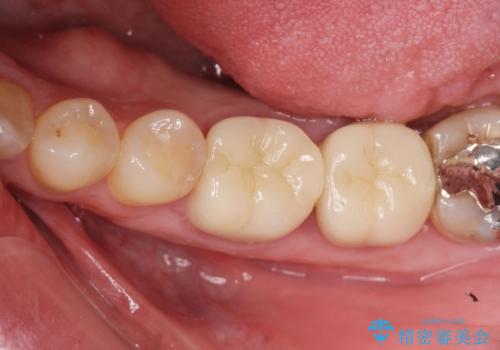

適合の良いセラミック治療をおこなったことで、歯ブラシがしやすくなり銀歯の見た目だけでなく歯ぐきの状態も大幅に改善することができました。